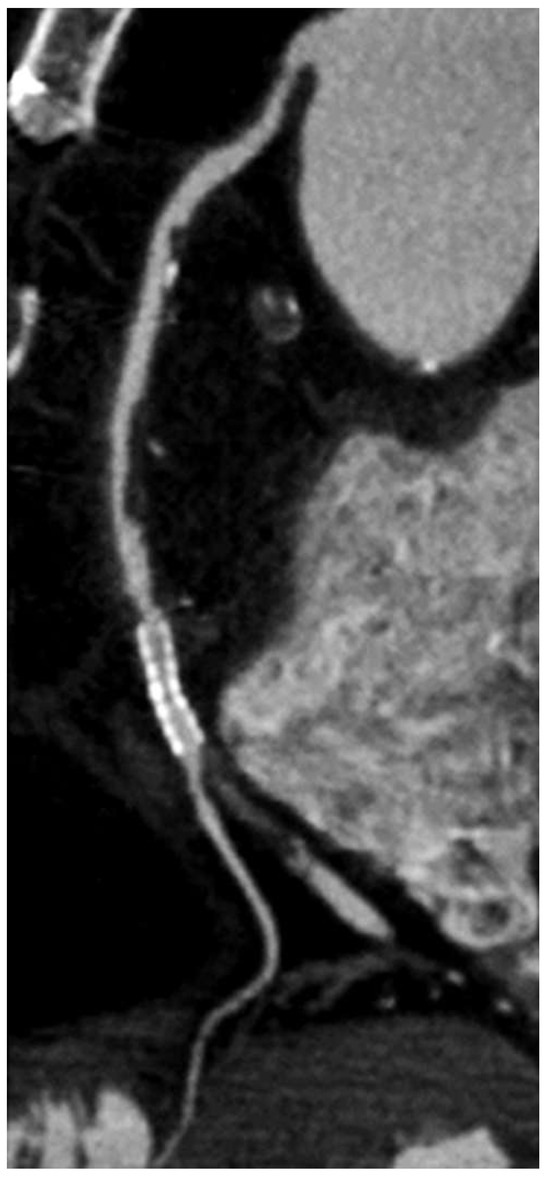

Computed tomography coronary angiography (CTCA) is a potential risk-stratifying tool in asymptomatic primary care subjects. Its diagnostic accuracy is comparable to conventional coronary angiography (CCA), which is an invasive procedure. By using CTCA, noncalcified plaques in the arterial wall (“noncalcified plaque”) and luminal narrowings (“coronary stenoses”) can be detected with injection of contrast media (Figure 2). However, image quality may be reduced in severely calcified coronary segments causing “pseudostenosis”, thus reducing specificity and positive predictive values [37]. Breathing artefacts, staircase artefacts and artefacts due to irregular heartbeats or cardiac devices (pacemakers, implanted defibrillators) may diminish image quality and result in nondiagnostic scans.

Figure 2. Computed tomography coronary angiography in a patient with known coronary artery disease. Here the right coronary artery is displayed using a multiplanar reconstruction. Note the stent in the midportion of the right coronary artery just before the bifurcation, the proximal stenosis and multiple plaques (calcified and noncalcified).